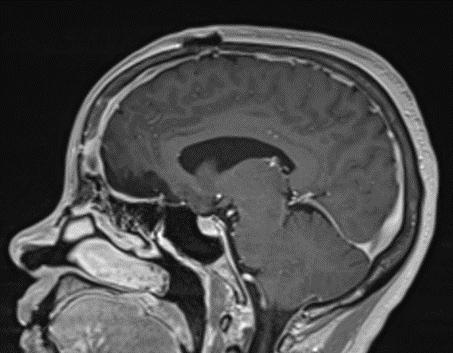

This is a 49-year-old otherwise healthy female who presented with bifrontal and retro-orbital headaches, behavioral changes, and forgetfulness. Symptoms have been progressively worsening over the past month. Her neurologic exam revealed a pronator drift, otherwise was unremarkable. MRI brain demonstrated a large extra-axial homogeneously enhancing mass of the anterior cranial fossa, resulting in significant mass effect and vasogenic edema (Figure 1a and 2a). Imaging was most consistent with a planum sphenoidale meningioma. She was referred to Dr. Xavier Gaudin for neurosurgical evaluation.

Figure 1a – Preoperative MRI demonstrating an extra-axial enhancing mass of the anterior cranial fossa.